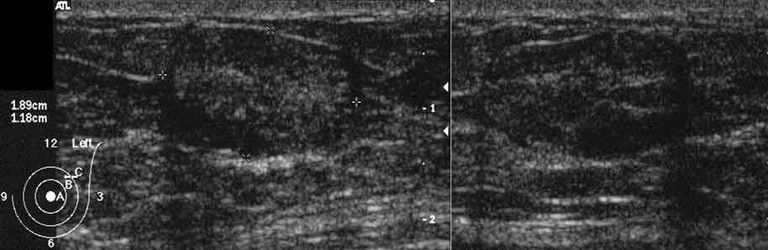

Epididymis anatomy

• A - head of epididymis

• B - body of epididymis

• C - tail of epididymis

• D - vas deferens